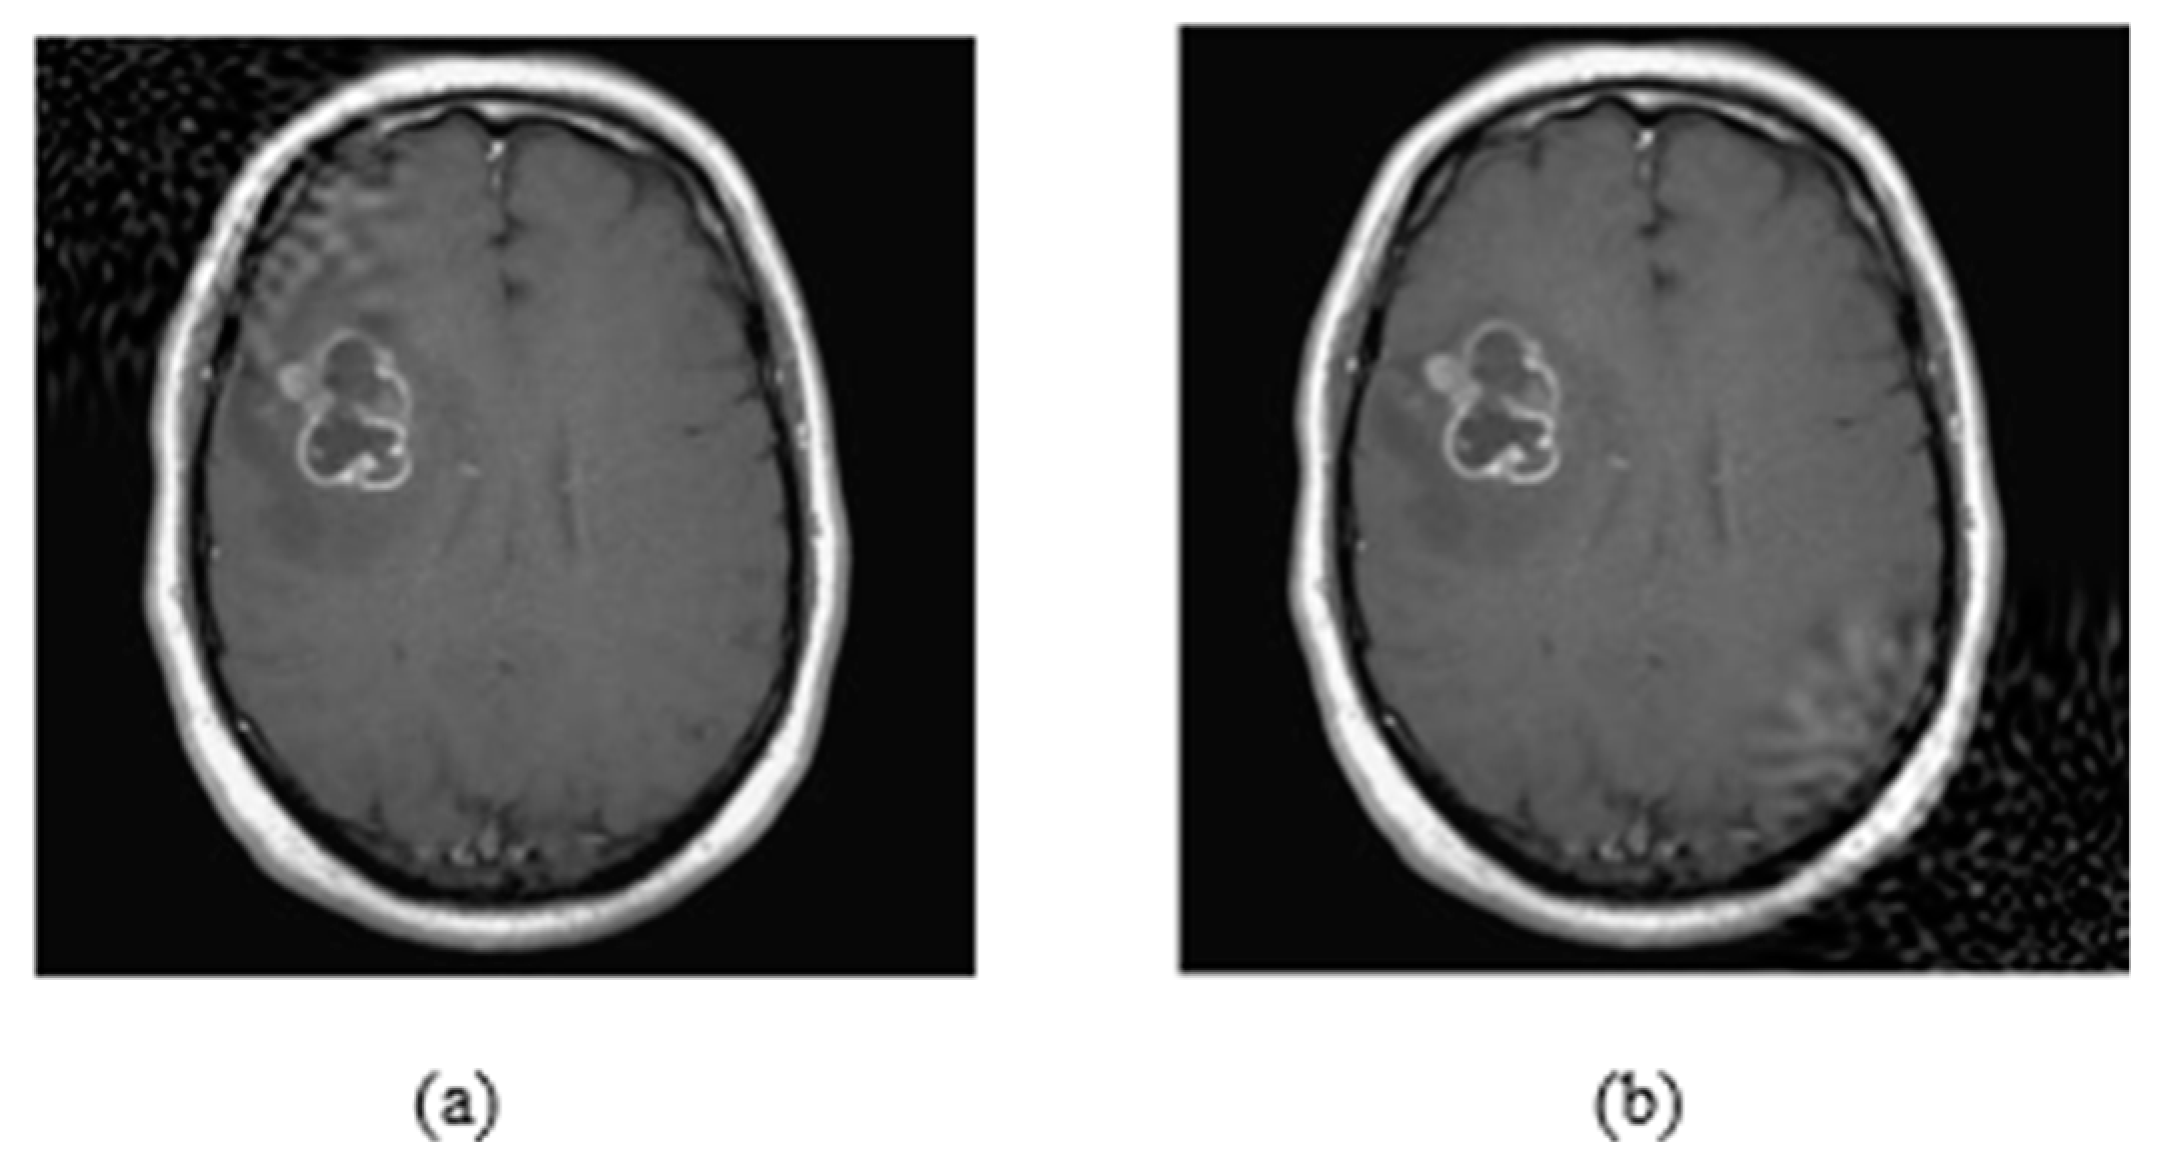

Figure 3.

(a) Watermark embedding with p1 = 0.1 and p2 = 0.1, (b) Watermark embedding with p1 = 0.9 and p2 = 0.9.

As it is shown in Figure 3a, the watermarking is embedded on the upper left corner, as the p parameters are equal to 0.1, while in (b) the watermarking was embedded on the bottom right corner because p values are equal to 0.9. Both p values range from 0.1 to 0.9 by representing all local points of the image. In Figure 4, it is presented how the embedding strength affects the distortion of an image while the other parameters are constant (L-bit = 1000, p1 = 0.1, p2 = 0.1), and in Figure 5 the perturbation is presented from L-bit length (embedding strength = 300, p1 = 0.1, p2 = 0.1). Embedding strength controls the limit of watermark information that is inserted in the image. A large embedding strength provides more robustness, but it is also more perceptible at the same time.